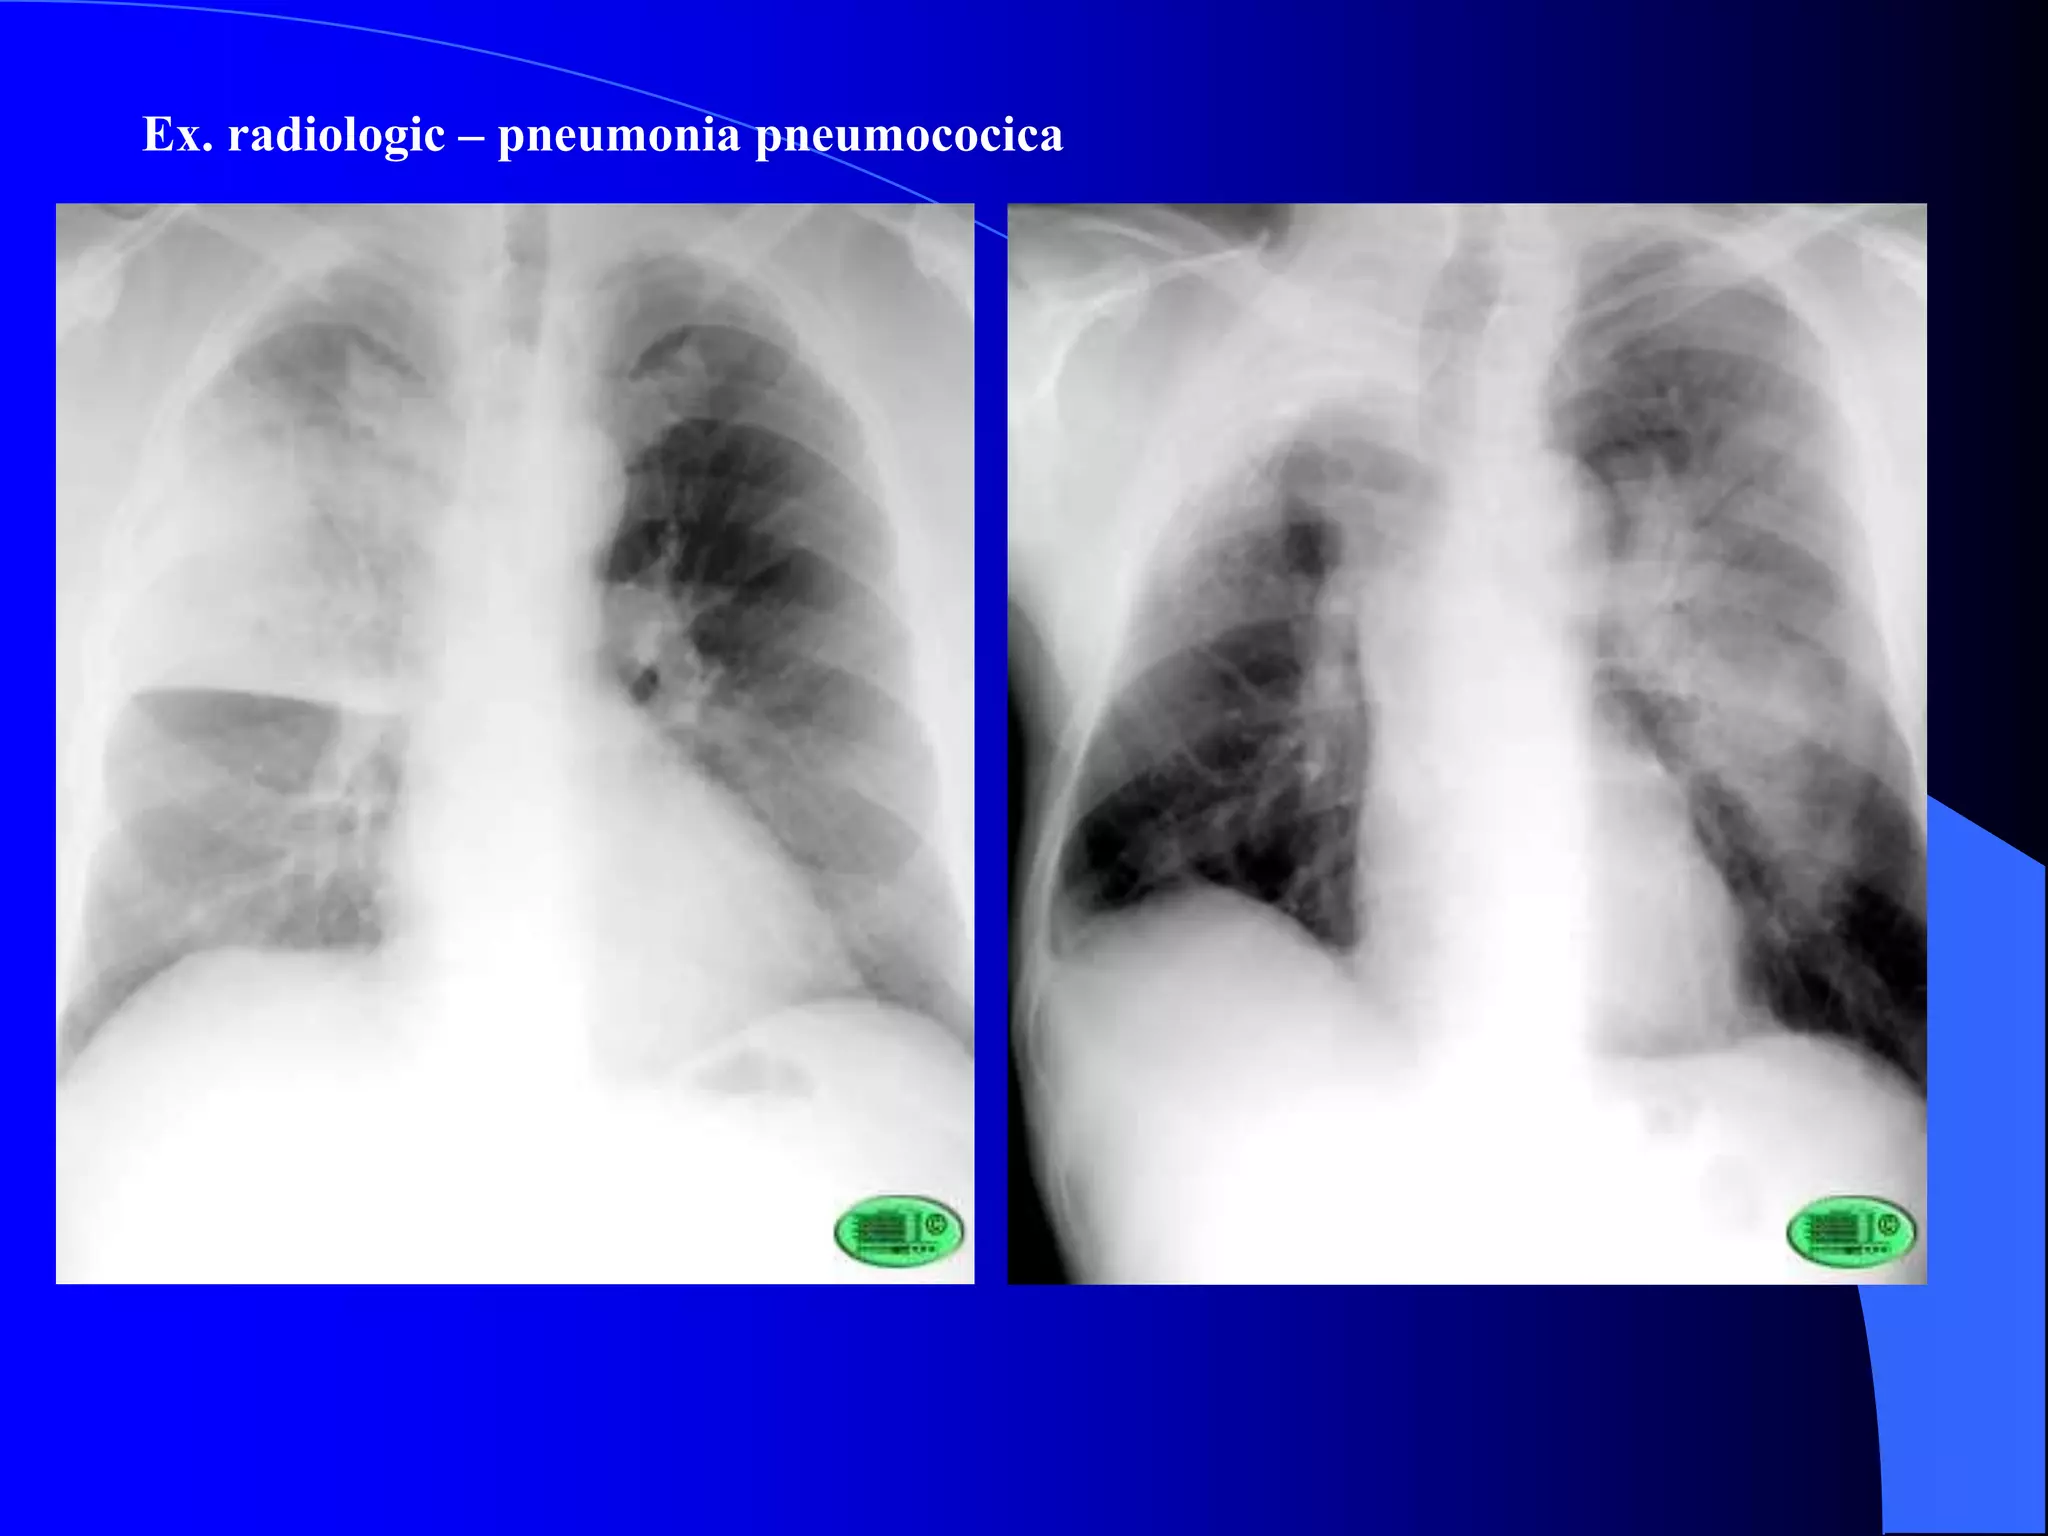

Ex. radiologic (static si dinamic)

- permite dg. de localizare, stadiu evolutiv, tendinta la extindere, complicatii

 static: opacitate omogena, intensitate subcostala, de forma triunghiulara, cu varful la

hil si baza la periferie; neomogena in st. de resorbtie

 dinamic: opacitatea contrasteaza mai bine in inspir, omogena, intensitate subcostala; in

faza de resorbtie → aspect “in tabla de sah”

Ex. radiologic – pneumonia pneumococica